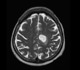

Image Credit: pang_oasis / Shutterstock.com

The techniques typically used to diagnose gliomas include assessment of medical history and symptoms, a neurological exam to test balance, reflexes, vision, hearing, and cognitive ability, magnetic resonance imaging (MRI) and/or computed tomography (CT) scans to create detailed images of the brain, as well as a biopsy to test small samples of the tumor under a microscope.

Therefore, a patient with a low-grade glioma is initially monitored through the use of MRI scans to assess how quickly the glioma is growing. This is referred to as “watchful waiting.” In cases of very slow-growing tumors, treatment may not be necessary until months or years later and, in some older individuals, the tumor may grow so slowly that treatment is never required.